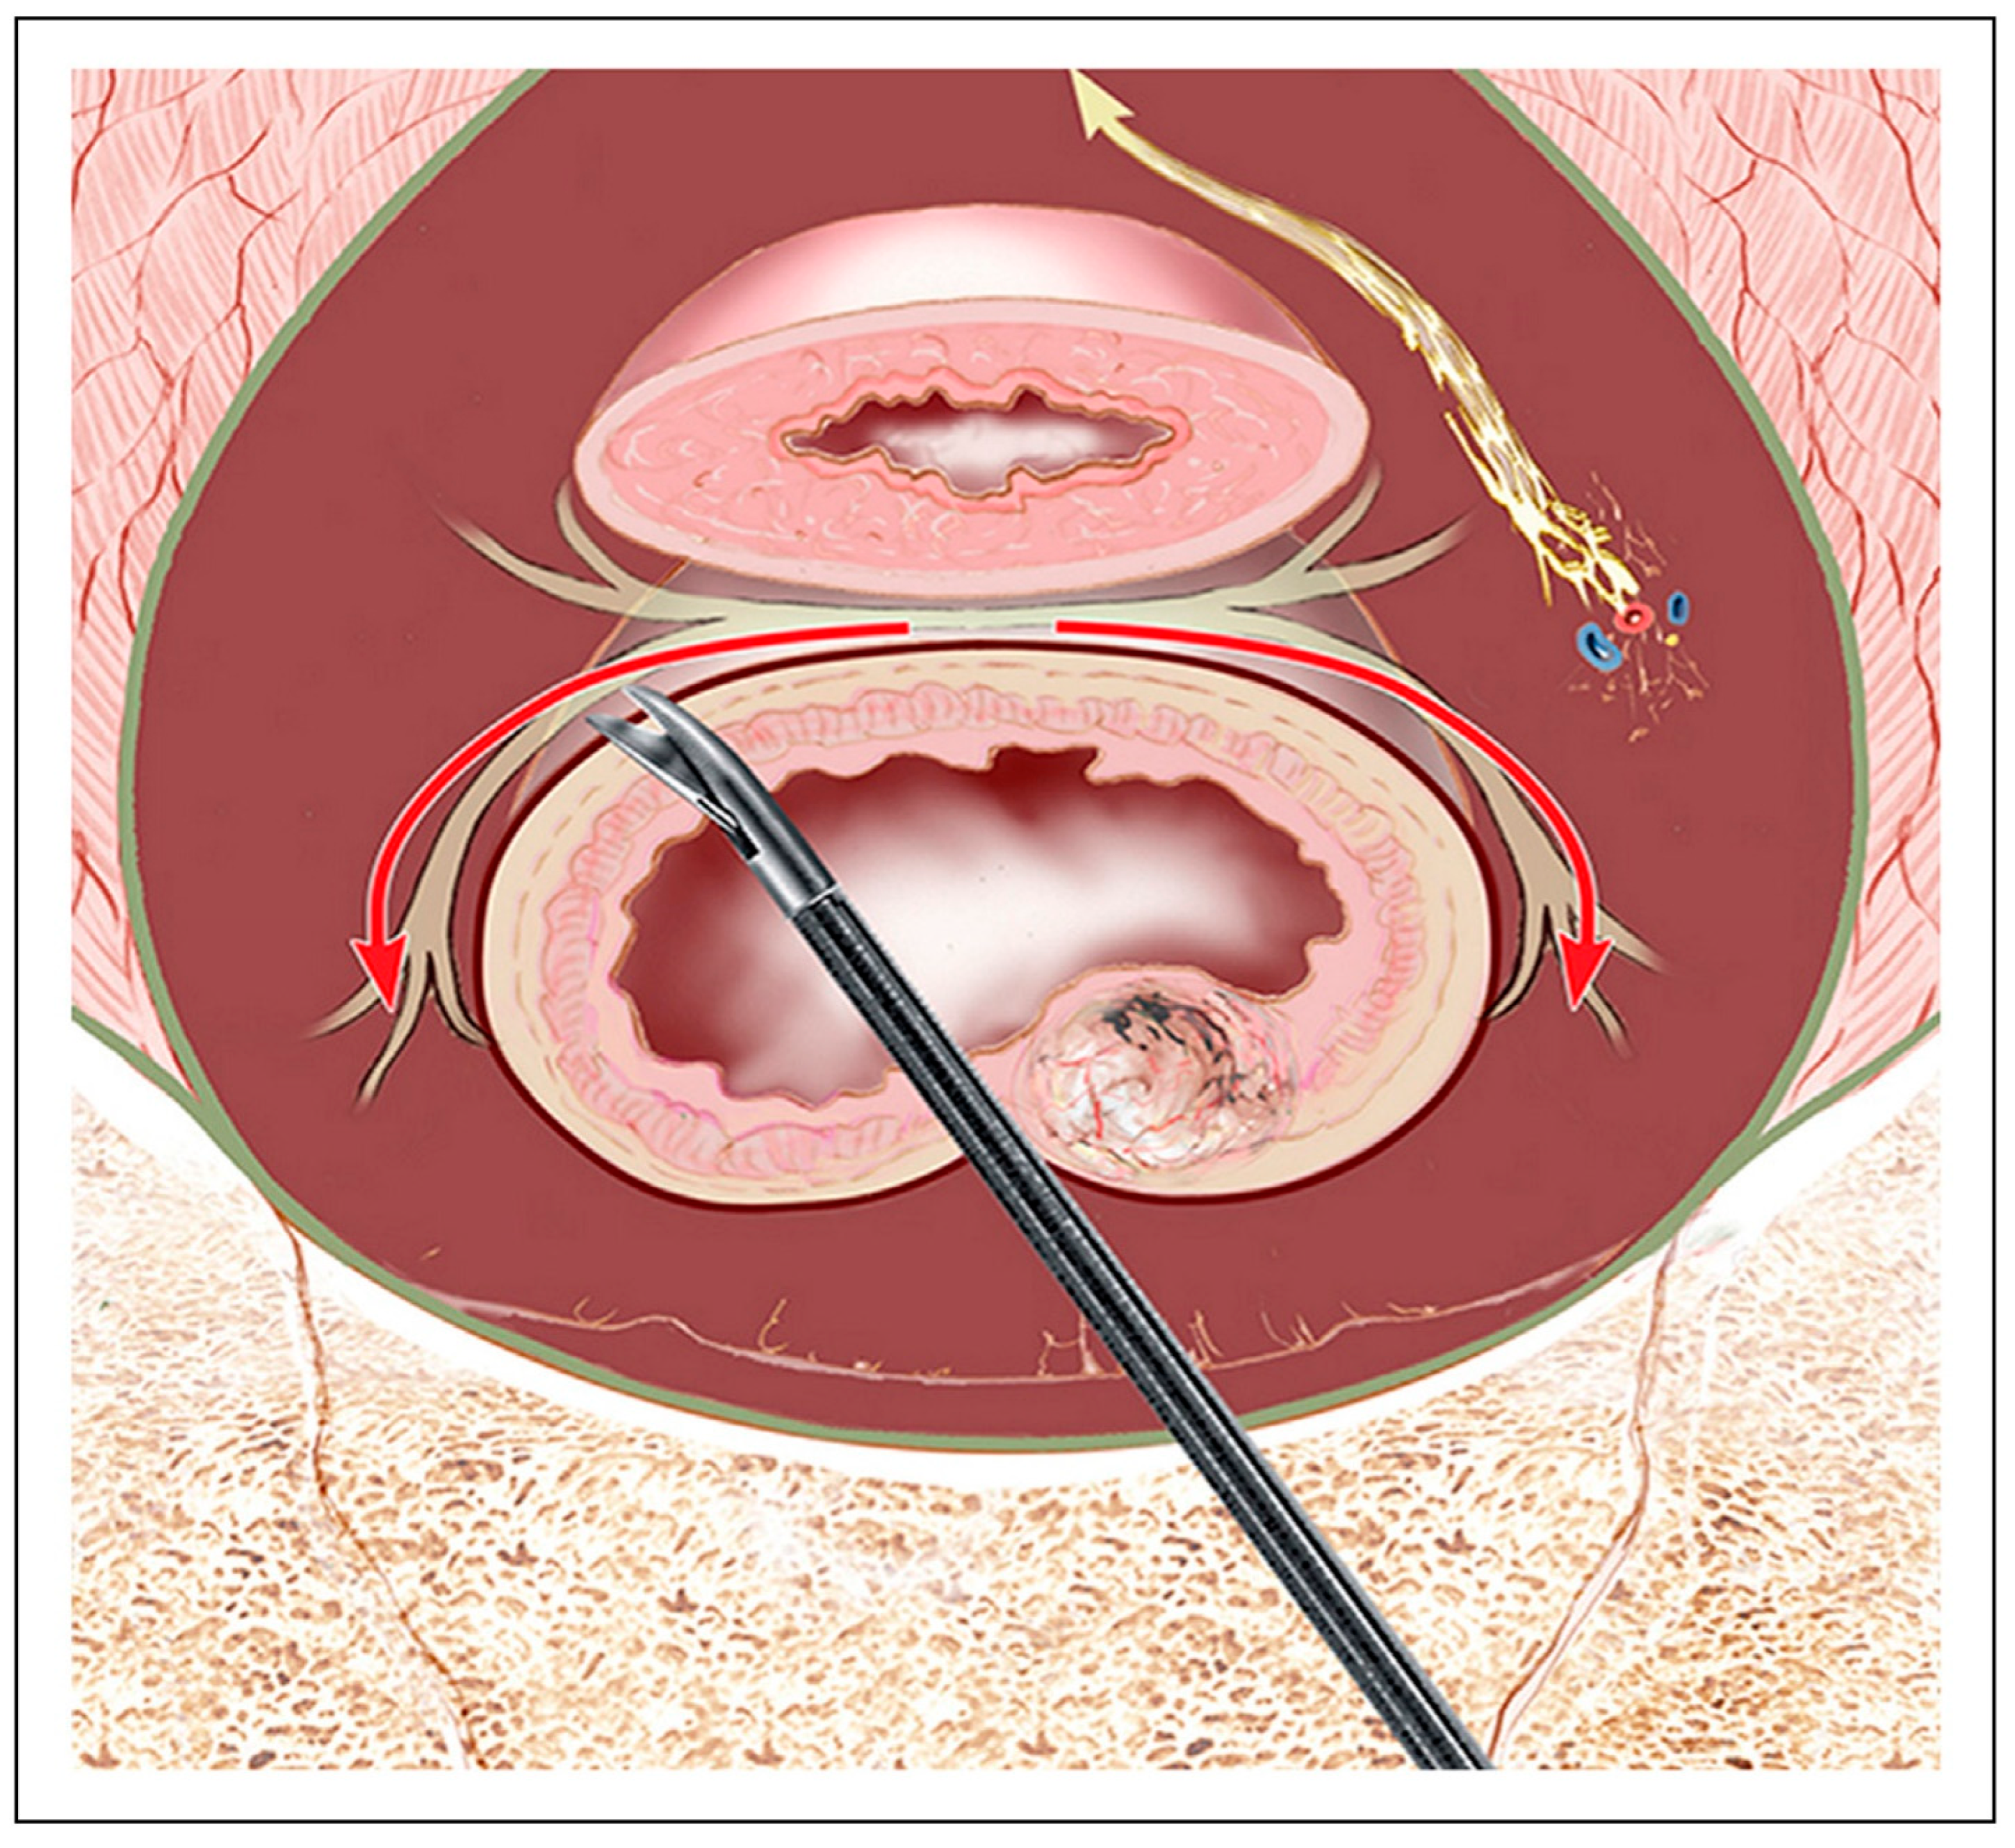

| Posterior Dissection | Sharp dissection in holy plane between fascia propria and presacral fascia | Superior hypogastric plexus, hypogastric nerves | [45,51] |

| Lateral Dissection | Dissect on the outer surface of the visceral/mesorectal fascia (fascia propria); clip/divide nervi recti and middle rectal vessels at mesorectal entry (≈4 & 8 o’clock); avoid behind-parietal-fascia skiving or skeletonizing ureter/iliac vessels. For the final release adjacent to the IHP, prefer sharp (cold) dissection over energy. | IHP, PSN; limits traction/thermal injury and lets plexus recoil laterally. | [26,44,45] |

| Anterior Dissection | Dissect behind Denonvilliers’ fascia or septum | Cavernous nerves, neurovascular bundles | [26,54] |

| Energy Device Modulation | Use minimal thermal spread devices near nerve planes; at/just off the IHP and NVBs, complete dissection with sharp, non-thermal technique (cold scissors/knife) to avoid lateral heat conduction. | Prevent lateral heat-induced nerve injury. | [44,45,54] |